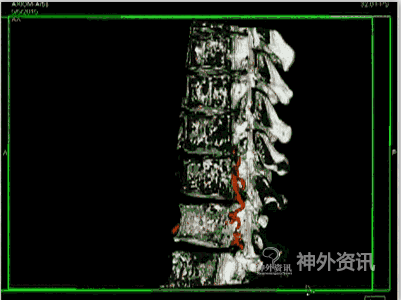

脊髓血管造影,尤其是经皮穿刺股动脉选择性脊髓血管造影,是诊断脊髓血管疾病的金标准。至今,由于影像技术、DSA血管造影机诸多后处理功能的进步,如三维成像技术(three-dimensional imaging technology;图1)、最大密度投影成像(maximum intensity projection,MIP;图2)、双容积重建(double volume,DV;图3)与三维影像融合技术(three dimensional image fusion technology;图4)及我们研究开发的三种技术的动态成像技术(dynamic image fusion technology),可以给出冠状位从前到后再从后到前、矢状位从左到右再从右到左、轴位从上到下再从下到上的全方位多角度动态立体解剖影像(图5),就更提高了对脊髓血管疾病诊断的认识和治疗水平。因此,应该说这些三维融合影像才是脊髓血管疾病诊断的金标准[1,2]。

图4: 右T12硬脊膜动静脉瘘(SDAVF),红色↑示瘘口,绿色↑示背侧引流静脉。A. 2D-DSA;B、C. 3D-DSA;D~F. 双容积重建冠状位、矢状位和轴位融合影像。

图4: G 动态双容积重建冠状位融合影像。

图4: H. 动态双容积重建矢状位融合影像。

图4: I. 动态双容积重建轴位融合影像。

图4: J~L. 最大密度投影(MIP)冠状位、矢状位和轴位融合影像。

图4: M. 动态旋转MIP。

图4: N~P. MRI/3D-DSA 三维融合冠状位、矢状位和轴位融合影像。